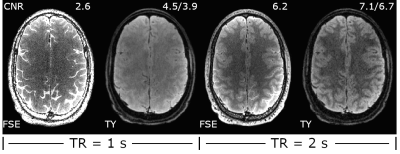

Simulated decay curves for under-sampled 3D FSE and TurboYarn along with flip angles for the 2 s TR sequences are illustrated in Figure 2. Designed constant signal is achieved with TurboYarn for both grey matter (GM) and WM, with average WM being 12% less than GM across the train. At the effective TE of 589 ms, 3D FSE WM and GM signal difference is similar at 11%. Images at different axial locations for the TR = 2 s TurboYarn sequence are shown in Figure 3 for subject #1. All images are presented raw without bias correction. Qualitative visual contrast between GM and WM is excellent, with demonstrative images from subject #2 shown in Figure 4. Background noise had an expected Rayleigh distribution (i.e. no constant offset) for TurboYarn, but not under-sampled 3D FSE. Thus, contrast-to-noise (CNR) was calculated from background noise only for TurboYarn, and alternatively from noise estimates in frontal WM regions for both sequences (Table 1). The largest CNR difference between comparative TurboYarn and FSE cases occurs for TR = 1 s. Fat and CSF are saturated for TurboYarn, but dominate images for FSE at TR = 1 s, though GM/WM contrast is visually low for both. All cases show increased CNR when longer trains are used (TR = 2 s), with TurboYarn showing superior CNR over 3D FSE in each comparison. At TR = 2 s, both FSE and TurboYarn display excellent GM/WM contrast, with slight improvements in the TurboYarn images.

Figure 4: CNR comparison for subject #2 for all four sequences. CNR increases as TR is increased in both 3D FSE and TurboYarn (TY). Both 3D FSE and TurboYarn suffer from low contrast between GM and WM at TR = 1 s.